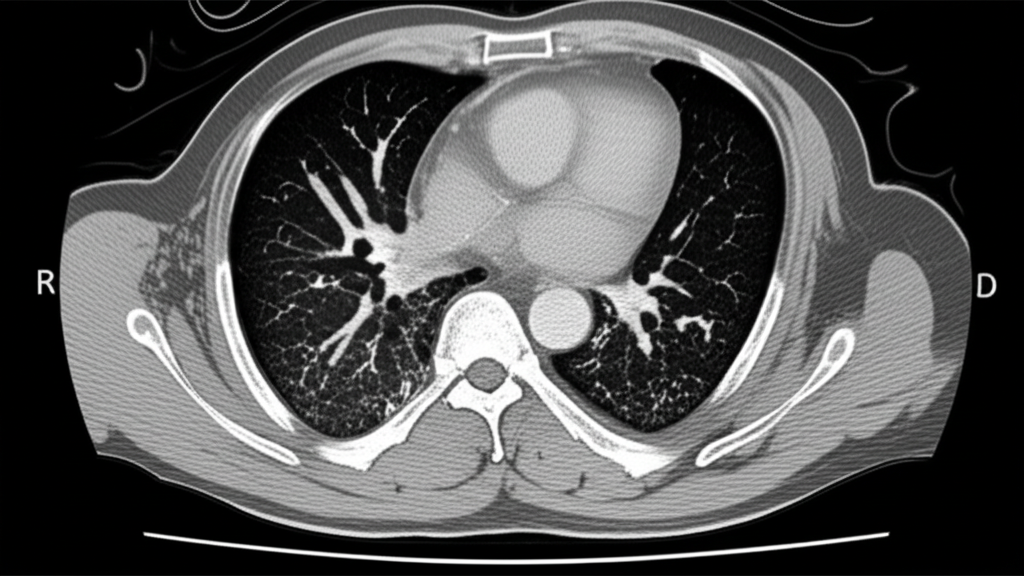

폐 CT는 폐 질환 진단에 매우 중요한 역할을 하는 영상 검사입니다. 흉부 X선 검사보다 훨씬 더 자세한 정보를 제공하여 폐암, 폐렴, 만성 폐쇄성 폐질환(COPD) 등 다양한 질환을 조기에 발견하고 정확하게 진단하는 데 도움을 줍니다. 건강 검진 시 폐 CT 검사를 고려하는 것은 건강한 삶을 유지하는 데 매우 현명한 선택입니다.

폐암 수술 전, 폐 CT는 종양의 크기, 위치, 주변 조직으로의 침범 여부 등을 정확하게 파악하는 데 사용됩니다. 이를 통해 최적의 수술 방법을 결정하고 수술 후 예후를 예측할 수 있습니다. 또한, 항암 치료나 방사선 치료 후 폐 CT를 통해 치료 효과를 평가하고 치료 계획을 조정하는 데에도 활용됩니다.

폐 CT는 폐암의 크기, 위치, 림프절 전이 여부 등을 정확하게 파악하여 병기를 결정하는 데 중요한 역할을 합니다. 조기 폐암의 경우 수술적 절제를 통해 완치를 기대할 수 있으며, 폐 CT는 이러한 조기 진단에 결정적인 기여를 합니다.